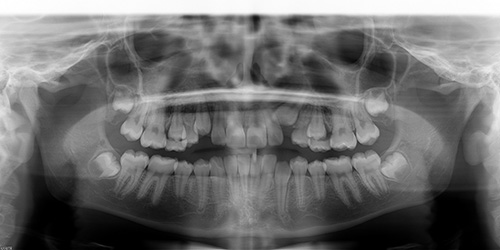

At the records appointment photos and 3D models of the teeth are made, as well as necessary x-rays and a comprehensive oral examination.